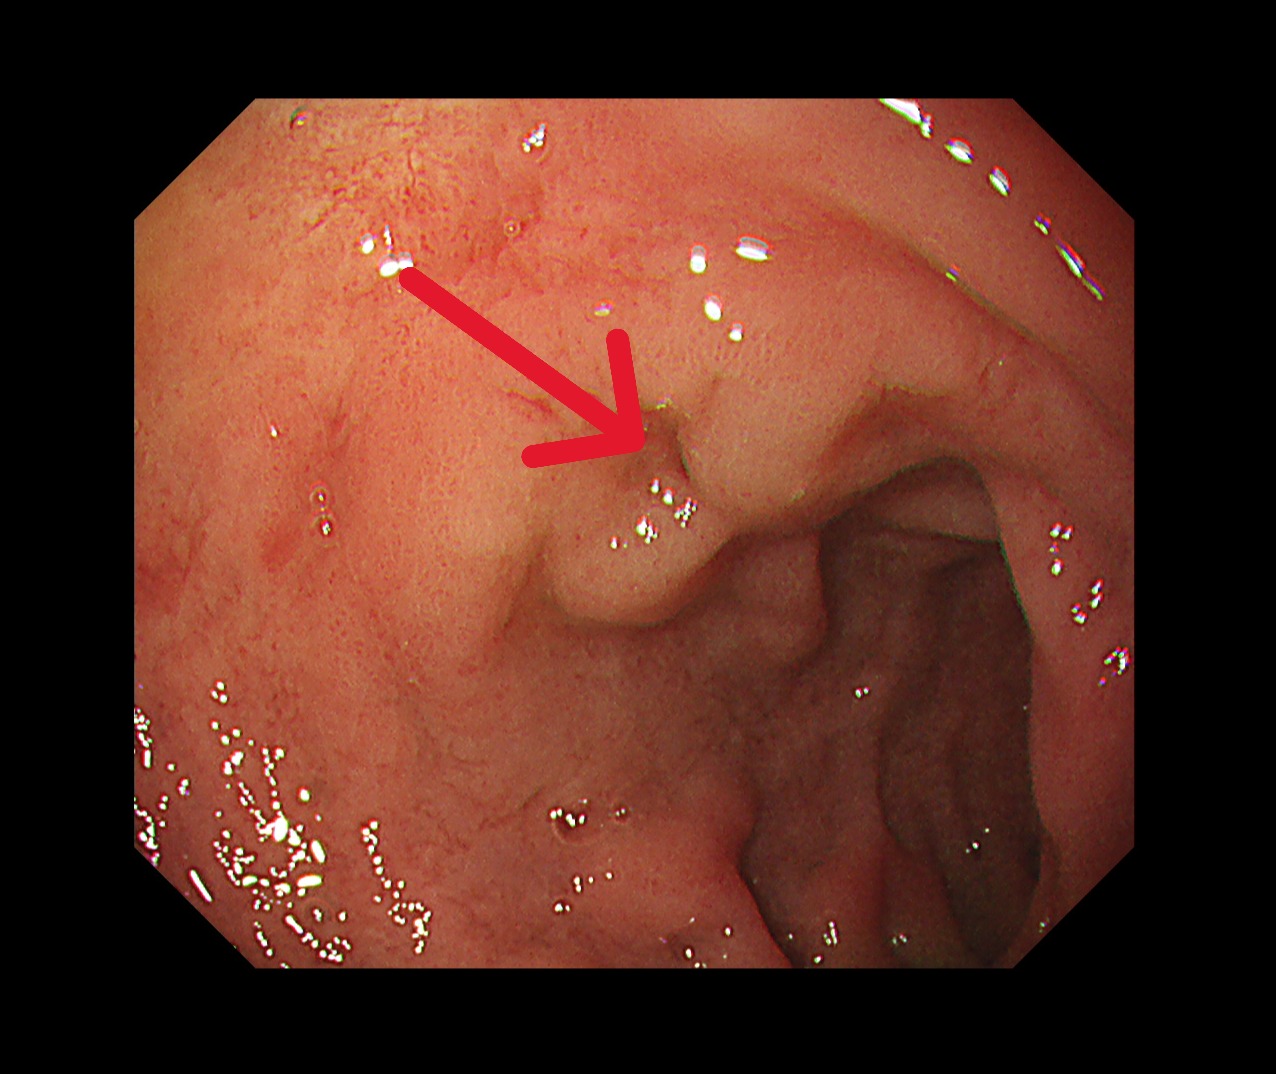

饒坤銘醫師向家屬逐一說明疾病情況與治療計畫。饒醫師建議採用國際間日益普及的「免疫治療合併化學治療」術前療法。此治療方式可提前觀察藥物反應、協助縮小腫瘤,並有助於降低手術風險,讓原本低迷的家庭重新看見希望。 胃鏡(治療後)

胃鏡(治療後)

經義大醫療外科團隊進一步評估後,患者體況已達手術標準,並順利接受胃部腫瘤切除手術。手術後的病理報告更帶來令人振奮的結果:腫瘤組織中未發現殘存癌細胞,成功達成「病理完全反應」。得知結果的當下,患者與家屬喜極而泣,醫療團隊也深感欣慰,這不僅是治療上的成功,更是病人、家屬與醫療團隊共同努力的成果。